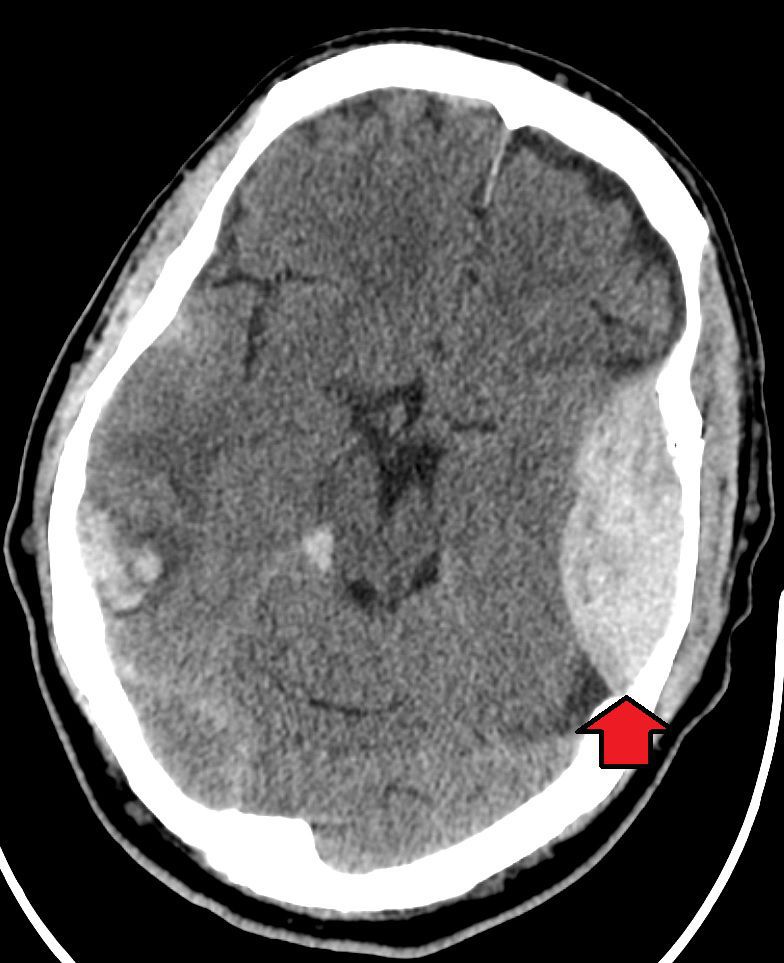

An epidural hematoma (EDH) is a collection of blood that forms between your skull and the dura mater, the outermost protective membrane covering your brain. The cause is usually an artery that gets torn by a skull fracture. Symptoms include severe headache and loss of consciousness